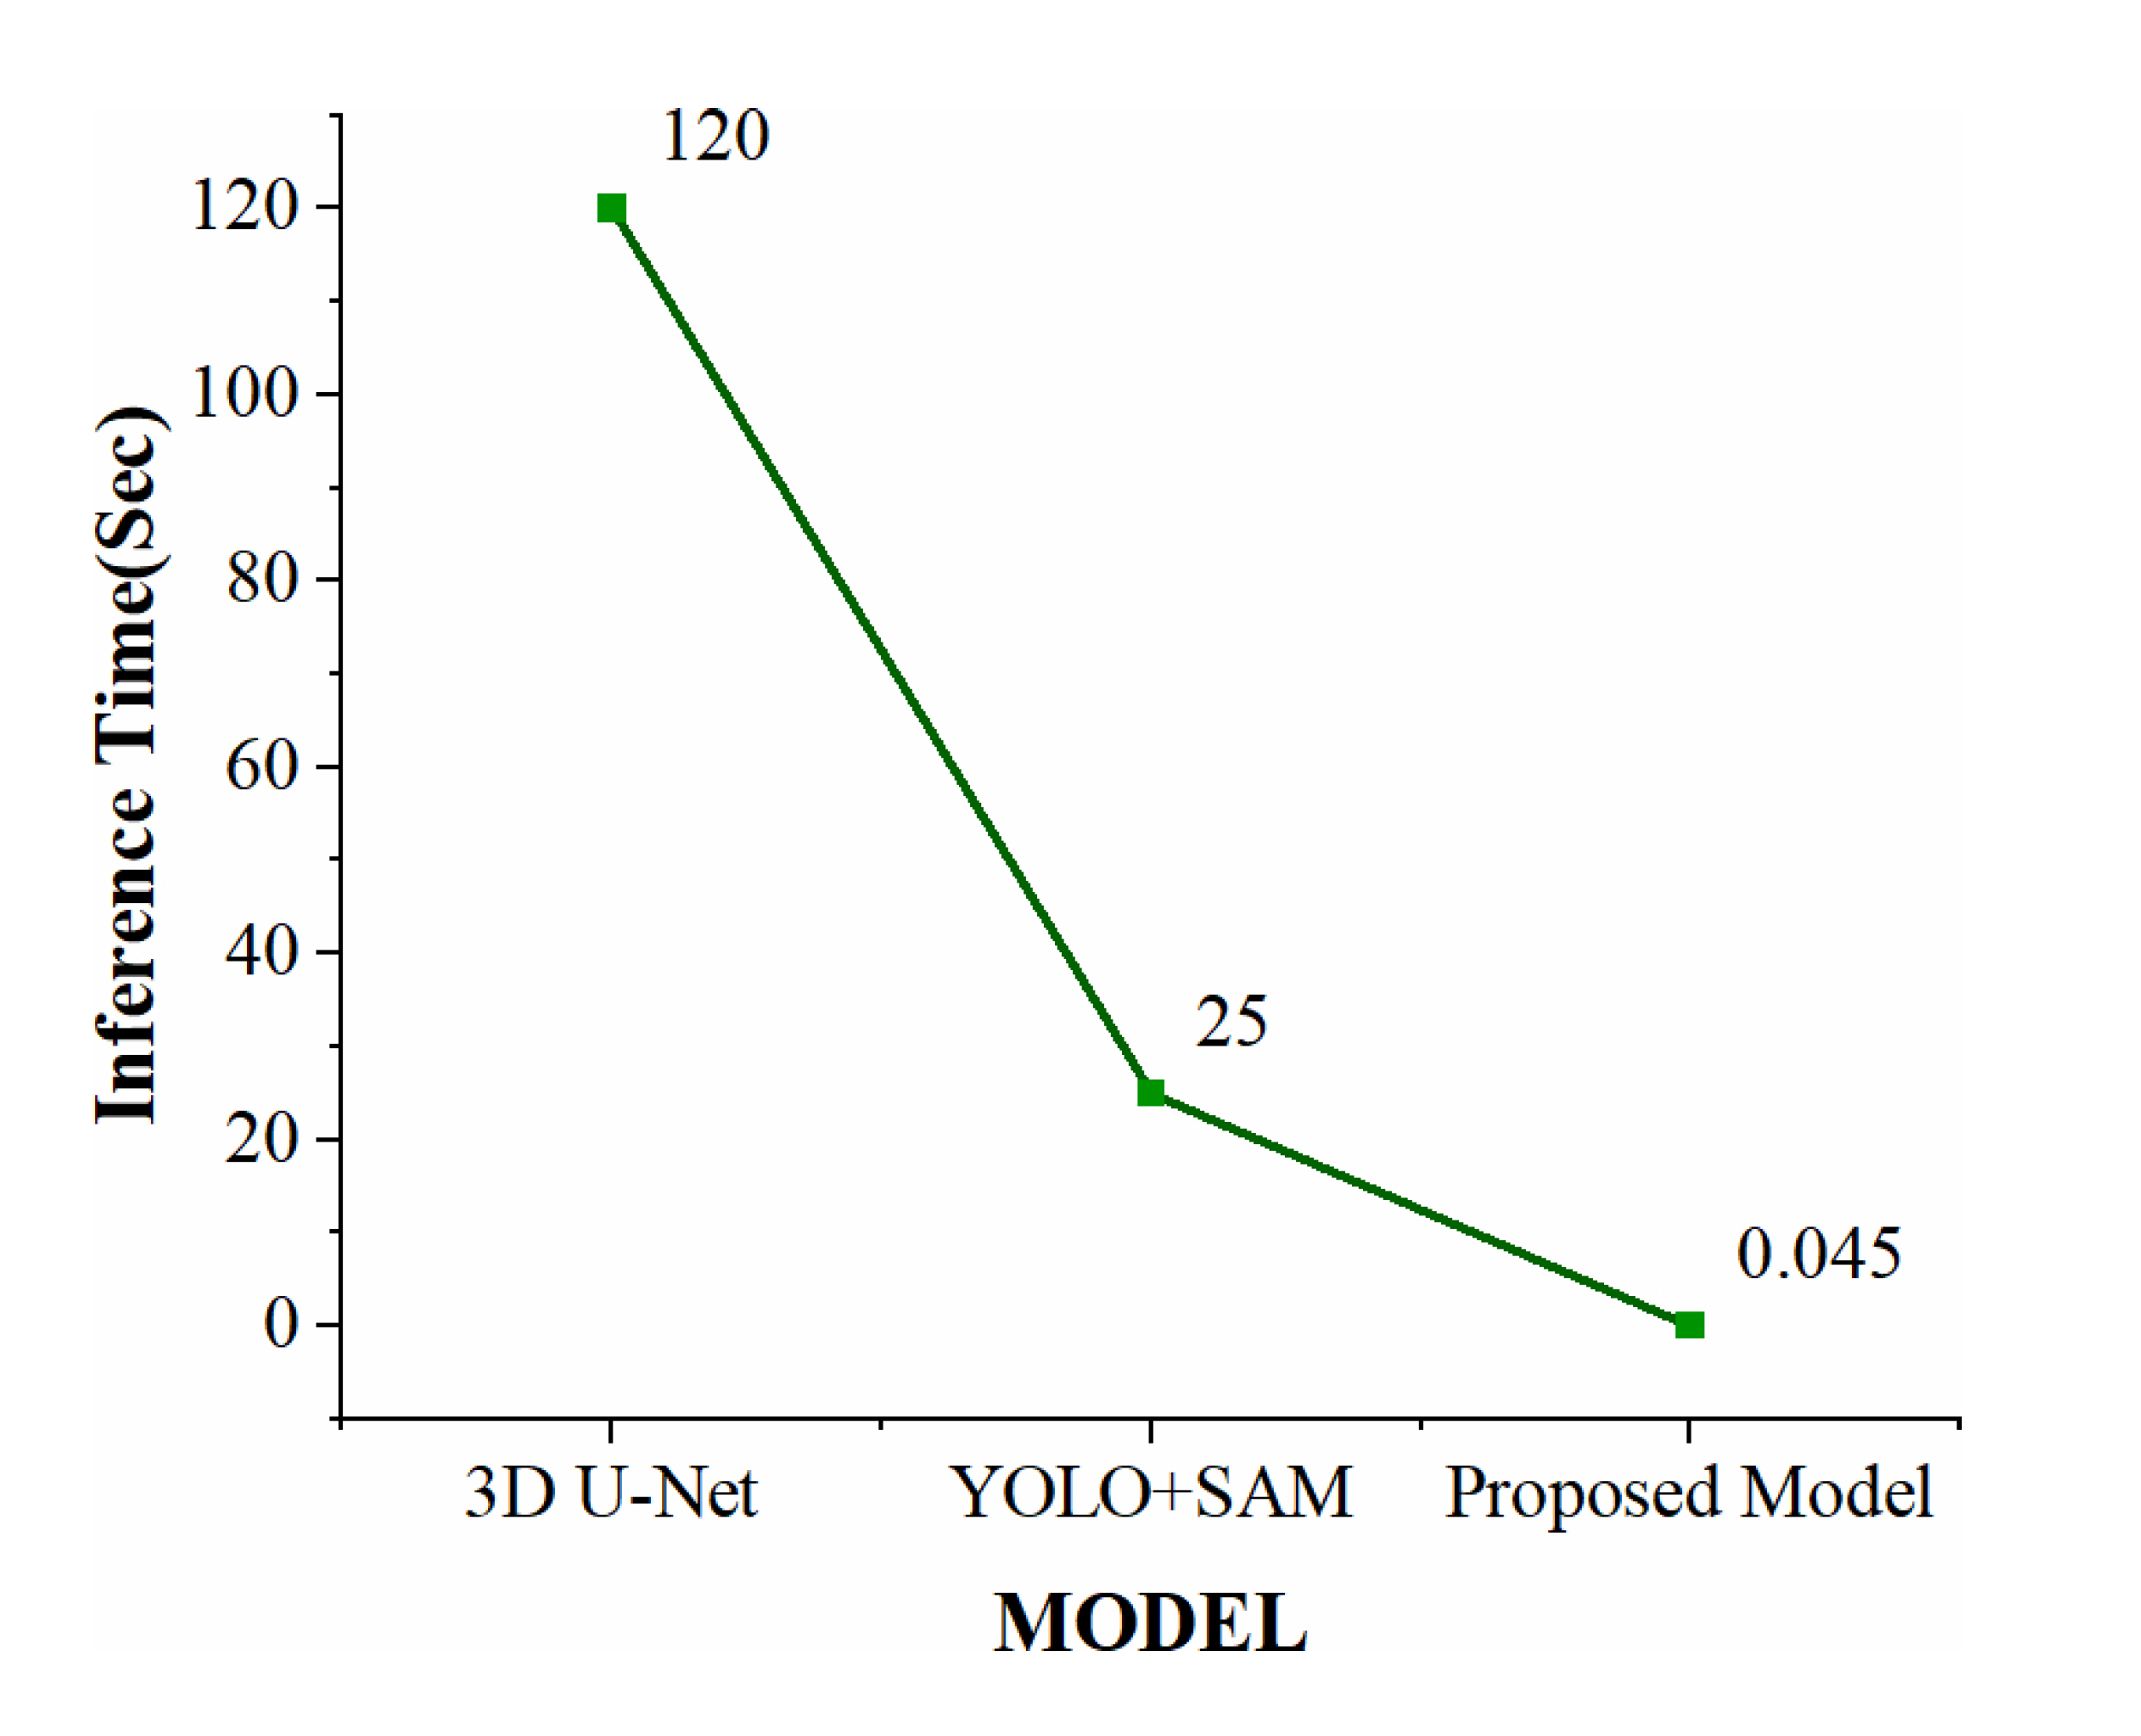

Inference times of the tumour segmentation model.

4.8. Detection Time

The evaluation of the models was carried out on a dataset comprising 91 frames, each with an image dimension of 640 × 640 pixels. Figure (13) represents the inference time for different models. The inference time for the 3D U-Net model was approximately 2 minutes to complete the tumour segmentation process, while the YOLO + SAM model required 15 to 25 seconds. In contrast, our proposed model required only 40–45 milliseconds to segment the tumour. Table 6 shows a comparison of inference times for different state-of-the-art models. Due to its significantly reduced inference time, the YOLOv12 + SAM 2 model was better suited for practical MRI brain tumour segmentation applications, providing faster and reliable outcomes during real-time surgical procedures.

| S.No. | Model | Inference Time(sec) |

|---|---|---|

| 1. | 3D U-Net [37] | 120 |

| 2. | YOLO+SAM [24] | 25 |

| 3. | Proposed Model | 0.045 |